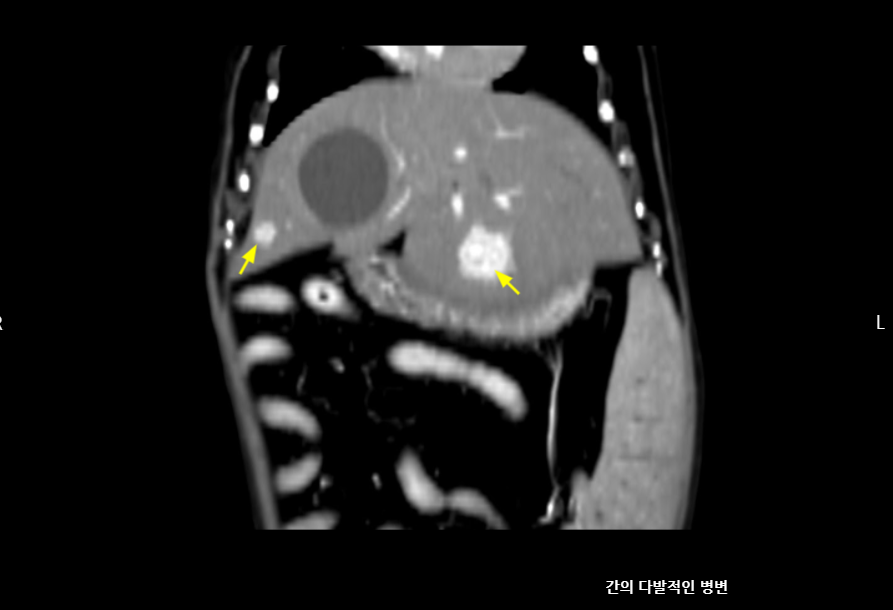

<메리의 CT사진>

또, 초음파와 CT검사를 통해 간과 비장, 췌장에 림프절이 커져있음을 확인하였습니다.

이는 주변 조직 전이를 의미하는 소견으로, 보호자님과 상의하에 추가적인 조직검사까지 진행하지는 않았습니다.

잠실ON동물의료센터에서는 이러한 여러 소견을 바탕으로 인슐린종(Insulinoma)로 잠정 진단하였으며 이에 대한 치료, 관리를 하기로 결정했습니다. 메리의 케이스는 여러 장기로의 전이가 의심되는 상황이었어요..